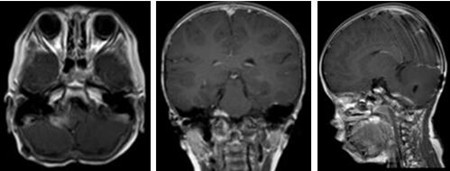

入院后完善术前检查,排除手术禁忌症后,杨宝应主任及其团队为薛仔实施“右侧桥小脑角区及上段脊髓右旁、四脑室内室管膜瘤切除术”,在显微镜下次全切除肿瘤,术后薛仔的症状明显好转,并辅以放化疗。

▲放化疗后